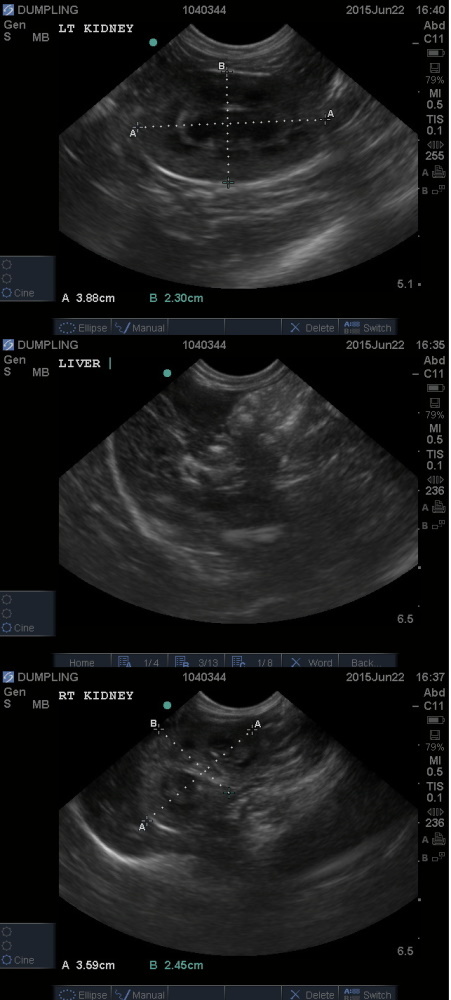

主題: 收容所帶出嚴重鼻氣管炎噴鼻血流產的貓媽媽 申請者姓名: 臺北市支持流浪貓絕育計劃協會 花色: 申請日期: 2015-06-24 18:17:10 申請者部落格: 申請者臉書網址: 所在縣市/合作醫院: 台北市/極光動物醫院 治療費用: 43425元 需求人數: 45人 已結案 (2022-05-13 15:07:15) 報名人員: LuLu(已付款)、Deb Lan(已付款)、Sheryl Sung(已付款)、anytamuffin(已付款)、Rebecca(已付款)、徐粉粉(已付款)、Joy(已付款)、Cherry Huang(已付款)、愛波(已付款)、Anthony Huang(已付款)、Juen-Nien Lin x2(已付款)、Yiying(已付款)、Ishin Ro(已付款)、Freesia Tsai(已付款)、wgs(已付款)、dolce(已付款)、Mia Chao(已付款)、Fionna Hsu(已付款)、王小慧 x2(已付款)、angel(已付款)、小朱(已付款)、白欣田、邱尚庸(已付款)、KiMi(已付款)、游玉晨(已付款)、Yan Lu(已付款)、徐南西(已付款)、Vivian(已付款)、廖千慧(已付款)、Patrick x2(已付款)、Candyfloss Hi(已付款)、vivian(已付款)、華庭沒媽媽的小奶貓(已付款)、YSL(已付款)、映月星辰(已付款)、Amanda Meng(已付款)、annlin(已付款)、娜塔莎(已付款)、May(已付款)、Mickey Han(已付款)、梁嘉儀 x3(已付款)、 候補人員: MIFFY5168、 動物病情說明: 志工前往新北市收容所帶出21支貓咪送往醫院進行結紮,志工打開籠子本來要抓其他的貓咪,而她卻默默走進提籃內,志工觀察有嚴重鼻氣管炎還噴鼻血,骨瘦如材,緊急送往醫院,嚴重脫水、全身無力削瘦、低體溫狀況危急,X光檢查還發現她懷有身孕,有六個寶寶,請大夜專職醫師看護,凌晨貓咪流產醫師緊急查看發現三隻小貓還有呼吸,而母貓很虛弱無法咬掉胎盤,更不用說將小貓的胎衣舔掉,醫師緊急處理保溫、餵奶,早上通知協會帶回,請代理媽媽進行哺乳,很遺憾因為小貓早產在晚上都當了小天使,而母貓繼續在醫院治療,志工前往探視,為了鼓勵貓咪就跟他說,如果好了就帶你回協會,不知道是貓有聽進去還是巧合,貓慢慢的恢復雖然白血球偏高但精神食慾尚可已出院帶回協會照顧。

住院醫療費用41715

1040627回診費用360元

1040630回診費用1350元

共計43425元